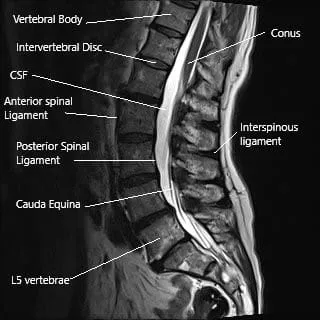

La médula espinal recorre el canal vertebral y da numerosas ramas (nervios espinales) a medida que avanza por el canal. El conducto vertebral se forma por las vértebras apiladas unas sobre otras. La lámina crea el techo del canal vertebral y el cuerpo vertebral forma el suelo.

El proceso espinoso es una proyección ósea en la parte posterior de las vértebras. Las proyecciones pueden notarse bajo la piel al pasar la mano por la línea media de la parte baja de la espalda. Los procesos espinosos proporcionan estabilidad y ayudan en el movimiento hacia atrás de la columna.

Resonancia magnética de la columna lumbar que muestra el ligamento interespinoso y el proceso espinoso.